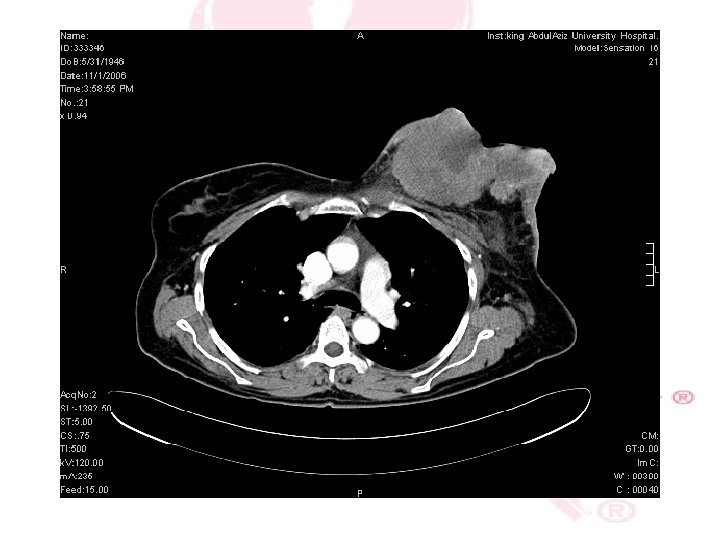

CT SCAN CHEST , ABDOMEN &PELVIS